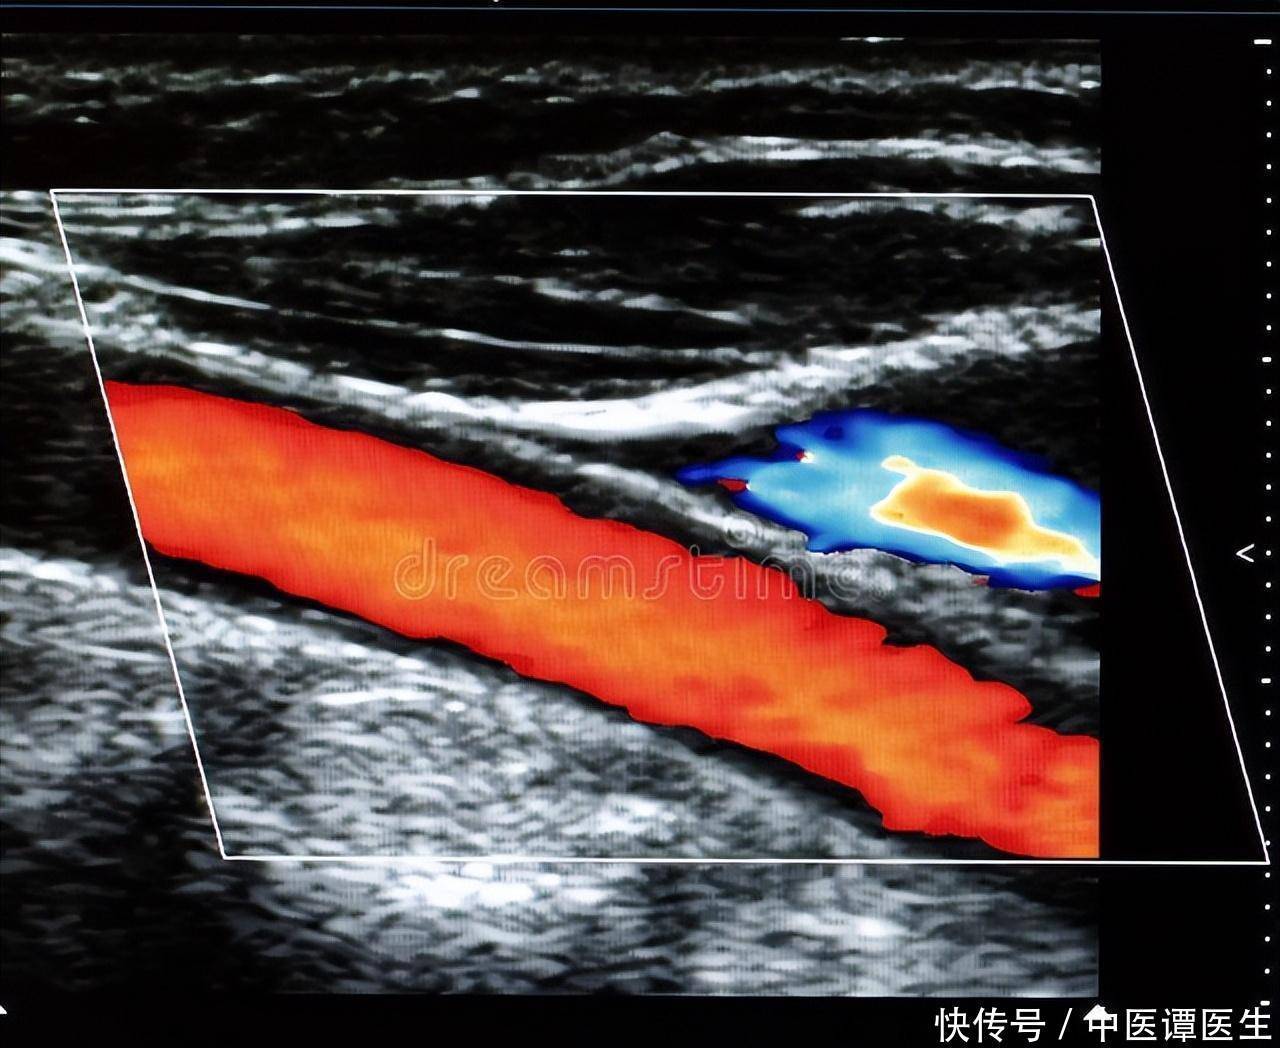

首先,我们需要了解,所谓的“青筋”,医学上被称为“静脉”,是血液在流向心脏的过程中经过的管道。相较于动脉,静脉的管壁更为纤薄,并且其内表面装备有瓣状结构,旨在阻止血液的逆向流动。手背上的静脉通常比较显眼,是因为这些静脉距离皮肤表面较近,而且血液流量较大,尤其在用力时,静脉会因为血液回流受阻而产生膨胀,从而表现出暴起的现象。

如果手背青筋暴起的现象持续不退,并伴有不适感,如手部肿胀、疼痛或功能受限等,应该及时就医,接受专业检查。医生可能会建议进行超声检查或血液检查,以确保没有潜在的静脉疾病、心脏问题或其他健康问题。